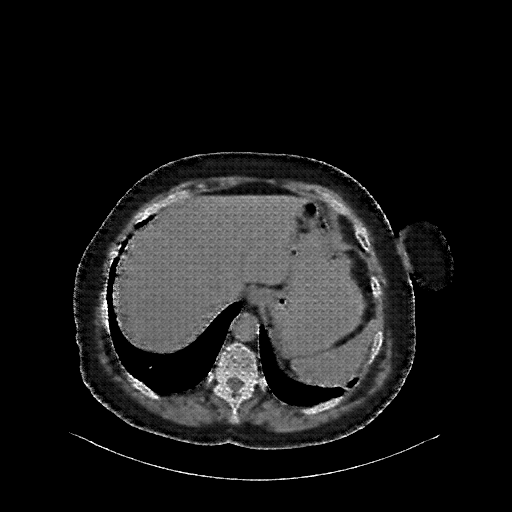

Reconstructed NATIVE CT scan (cycle consistency)

Full window (WL 1023.5, WW 4095 β†’ Low βˆ’1024, High +3071)

Generated VENOUS CT scan (A→B translation)